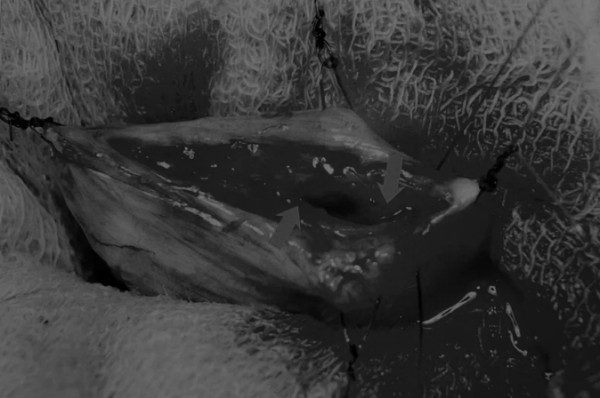

在牵引缝线之间选择血管扩张较差的区域用手术刀切开膀胱壁(图3)。在牵引缝合线之间用手术刀在血管不良的区域做切口。切开膀胱壁后,膀胱内的手术可按手术方案实施,例如取出结石(图4)。

图4 这张图显示了从膀胱中取出的大量结石